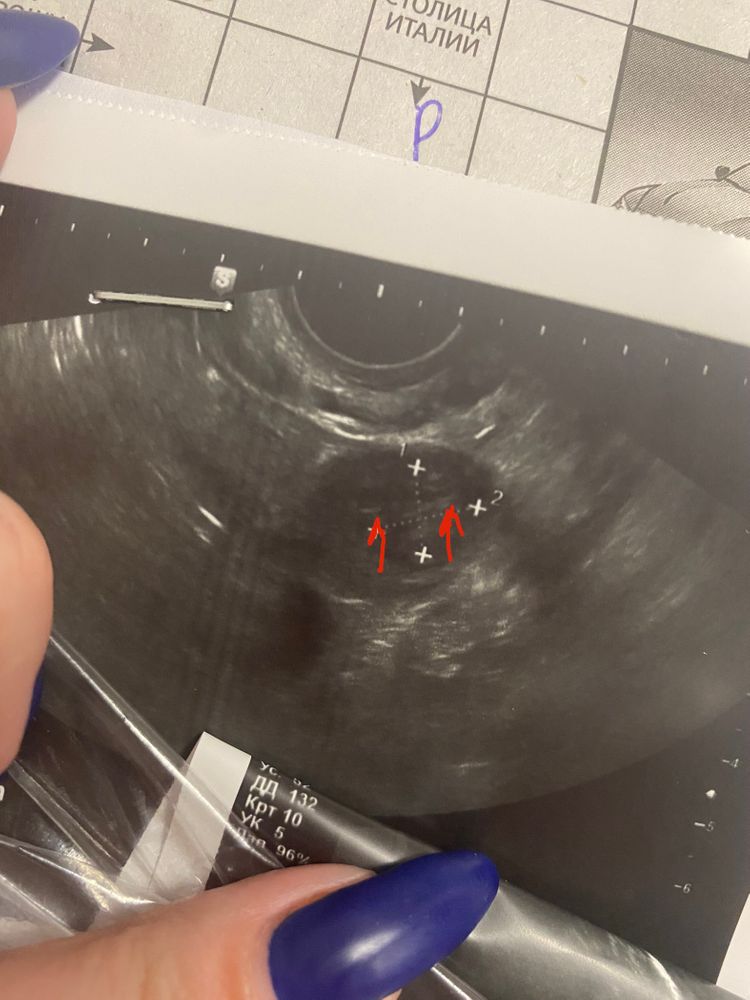

Оказалось два?)

Кукизавр, сказали «одного видим точно, а вот эта белая точечка не можем сказать что»😂 иду на узи в 8 недель, в чт, посмотрим, что там)))

Похоже на то. У меня тож так было, оказалось - два)

Elizabeth Budkevich, нет, дихориальная диамниотическая двойня.) У меня так выглядели два плодных яйца в полости матки, и потому мне кажется, что у вас вполне могут так выглядеть два малышка в одном плодном яйце

два кругляшочка!)))) Поздравляю!